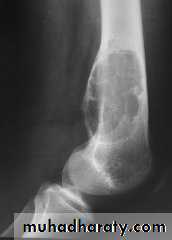

XR : lytic lesion + flecks of calcification

Rx : curettage + bone graftPicture 4. Frontal radiograph of the right thigh demonstrates coarse calcifications in the distal femur.